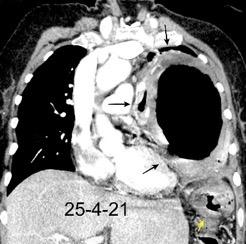

Tromboembolismo pulmonar.

Frecuencia del derrame:

Rx: 32%. TC: 47%

Unilateral. 85%

< 1/3 del hemitórax: 90%

Todos exudados

58% con eritrocitos

21% tabicación lo que causa demora en el diagnóstico

TEP. Empiema pleural. Atelectasia redonda

Porcel JM et al. Analysis of pleural effusions in acute pulmonary embolism: radiological and pleural fluid data from 230 patients. Respirology 2007/ Iguchi T et al. Desquamation of the subpleural lung parenchyma caused by empyema after pulmonary embolism: A case report. Respirol Case Rep. 2022 .